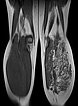

Die koronare T1-gewichtete native MRT zeigt eine intramuskuläre, gefäßreiche Läsion (isointens zur Muskulatur) mit deutlich zwischengelagertem hyperintensem Fettgewebe, mehr als bei einer normalen venösen Malformation üblich.

In der axialen T2-gewichteten MRT des linken Unterschenkels finden sich mehrere dilatierte, dysplastische Venen im Sinne einer venösen Malformation in der gesamten oberflächlichen Flexorenmuskulatur. Durch den niedrigen Durchfluss kommt es zur Stase des Blutes innerhalb der Malformation mit der Bildung von Flüssigkeits-Spiegeln. Praktisch der gesamte Muskel ist von Malformation und Fettgewebe durchsetzt. Großer Thrombus in einer dilatierten, dysplastischen Vene.